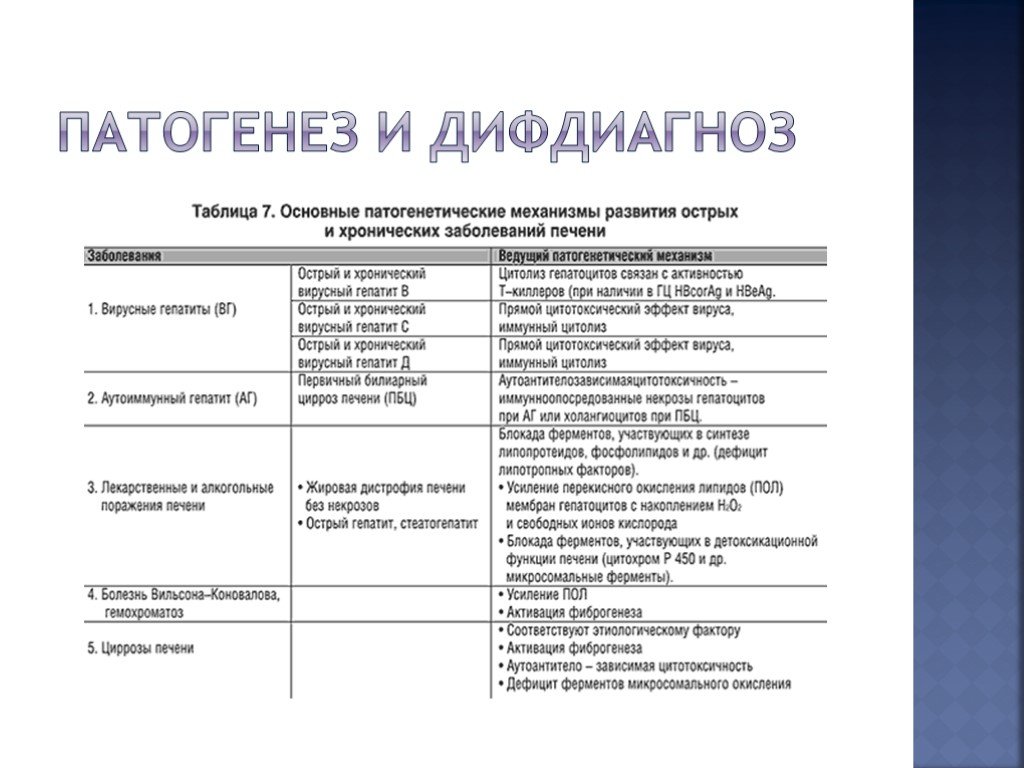

Дифференциальная диагностика заболеваний плевры